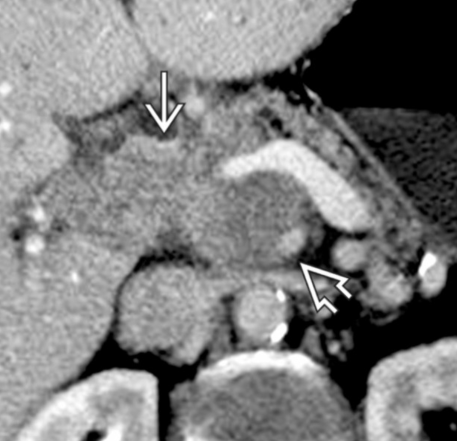

- Infiltration artérielle: <180° vs >180° et cranio-caudalement >2cm vs <2cm

- Infiltration veineuse: Contact, engainement, sténose, occlusion

- Infiltration de la lame rétroporte (entre l’AMS et l’uncus)

- Varices gastro-epiploiques si sténose VMS ou Veine splénique